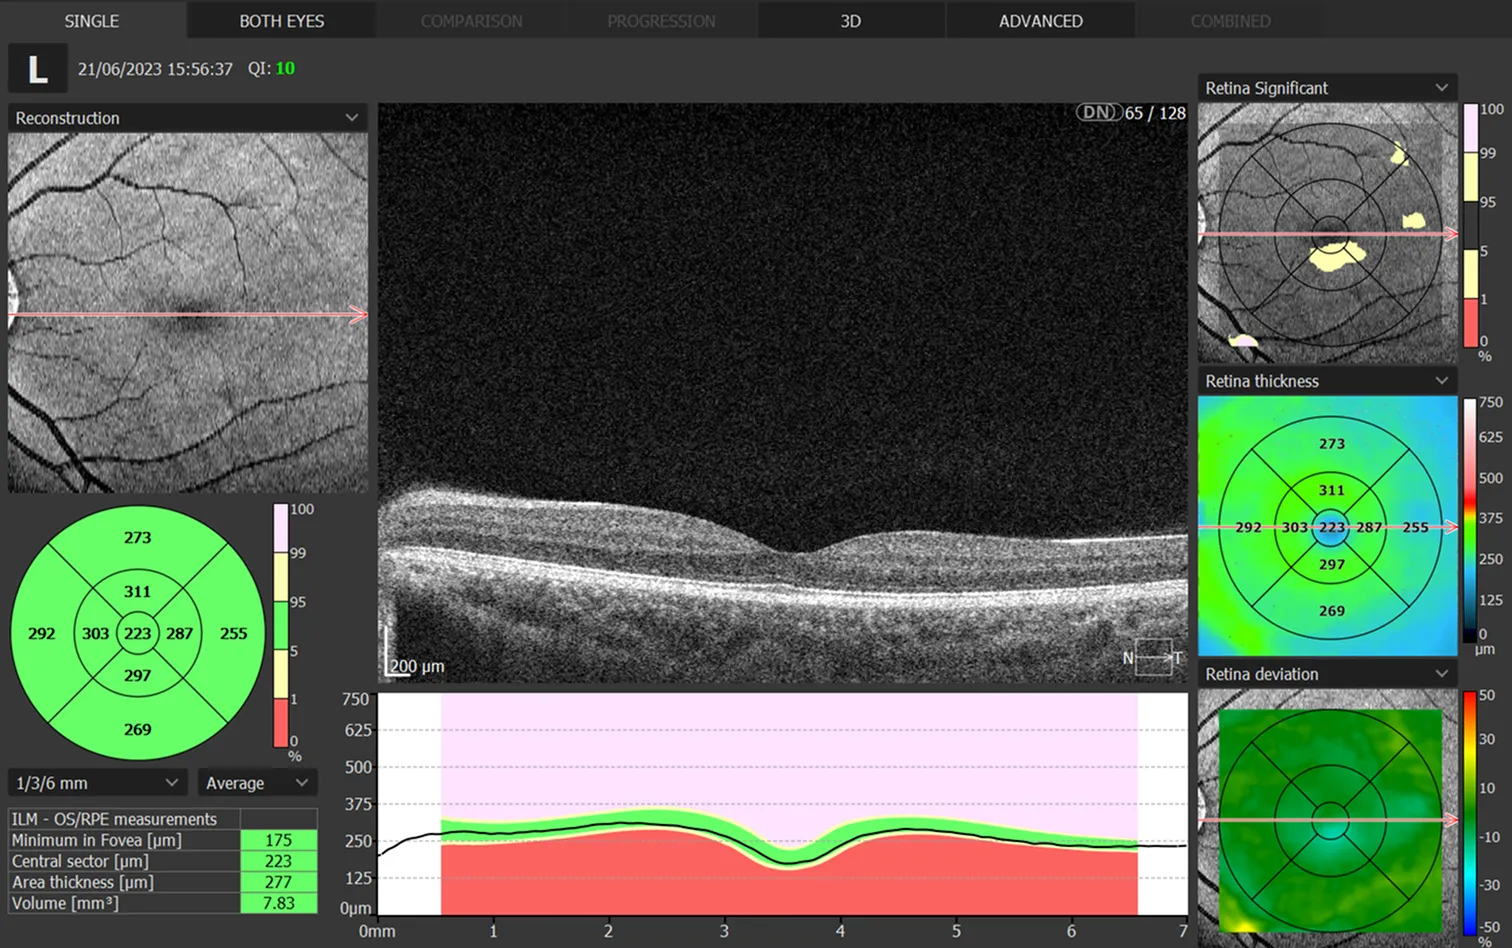

OCT SCANNING

At our Arnold, Bingham and West Bridgford practices, we are proud to now offer OCT (Ocular Coherence Tomography) scans as part of an enhanced eye examination.

OCT provides detailed retinal imaging, using light to safely examine the interior structure of the eye. This allows optometrists to catch serious conditions in their earliest stages.